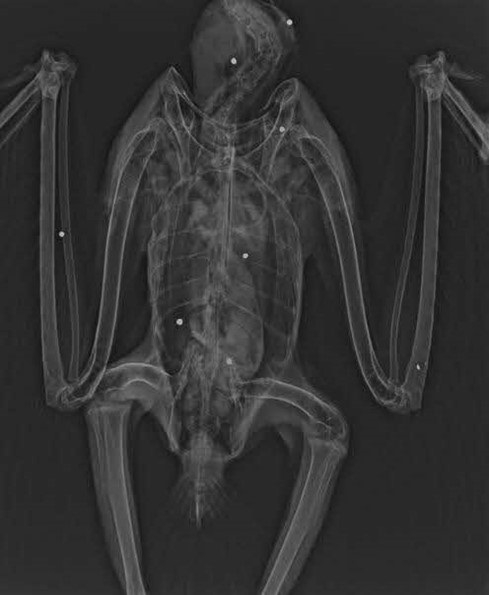

- レントゲン撮影において、骨折の他に、過去に被弾したと推測される合計10発の散弾を確認。

- 散弾は頸部から左脚にかけて確認され、その状態から、比較的近距離で正面方向から射撃された可能性が推測される。

写真:オジロワシのレントゲン写真(猛禽類医学研究所提供)

(白い点として映っているのが散弾。右側写真の赤丸が骨折部位)